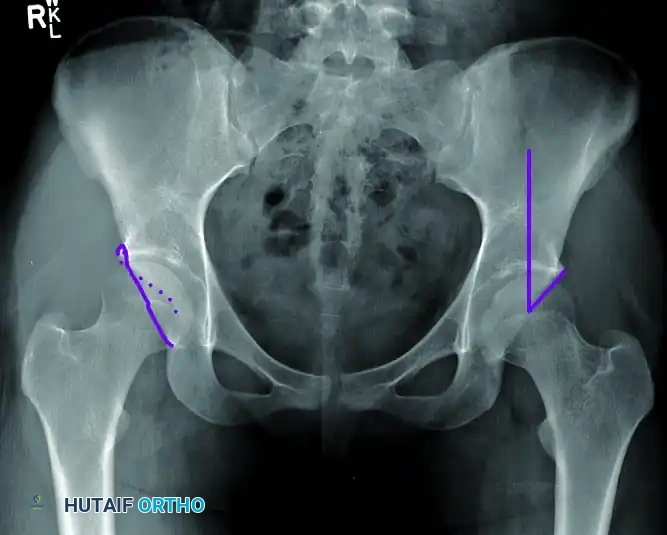

Radiographic Evaluation

A meticulous radiographic analysis is paramount for diagnosing FAI, classifying the morphology, and planning surgical intervention. The standard imaging protocol should include an anteroposterior (AP) pelvis, a false profile view, and lateral views of the hip (cross-table lateral, frog-leg lateral, or Dunn view).

The AP Pelvis Radiograph

The AP pelvis must be perfectly standardized to accurately assess acetabular version. A well-centered view is confirmed when the tip of the coccyx points directly to the symphysis pubis, and the distance between the coccyx and the symphysis is exactly 1 to 2 cm.

On this view, the surgeon must evaluate for:

* Coxa Profunda: Diagnosed when the floor of the acetabular fossa (teardrop) touches or crosses medial to the ilioischial line.

* Protrusio Acetabuli: Diagnosed when the femoral head itself lies medial to the ilioischial line.

* Acetabular Retroversion: Indicated by the "crossover sign." In a normal anteverted acetabulum, the anterior wall line remains medial to the posterior wall line. In retroversion, the anterior wall crosses lateral to the posterior wall in the superior aspect of the joint.

Center-Edge Angle (CEA):

The lateral center-edge angle of Wiberg assesses global acetabular coverage. It is formed by a vertical line drawn perpendicular to the transverse axis of the pelvis passing through the center of the femoral head, and a second line drawn from the center of the femoral head to the lateral edge of the acetabular sourcil. A CEA of less than 20 to 25 degrees indicates dysplasia (undercoverage), while an angle greater than 39 degrees suggests pincer overcoverage.

Lateral Radiographs and the Alpha Angle

Lateral views (particularly the 45-degree Dunn view) are optimal for evaluating femoral head sphericity and the anterior head-neck offset.

The Alpha Angle:

The alpha angle quantifies the severity of a cam lesion. It is constructed by drawing a best-fit concentric circle around the femoral head. A line is drawn through the central axis of the femoral neck to the center of the head. A second line is drawn from the center of the head to the exact point where the anterior cortical margin of the femoral head-neck junction deviates from the concentric circle. An alpha angle greater than 50 to 55 degrees is diagnostic of a cam deformity and loss of sphericity.